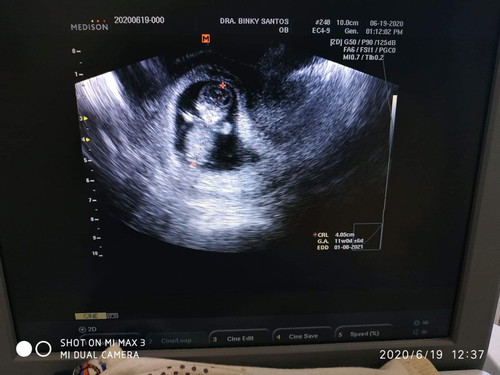

Ask ko lang po TVS kc gnwa sakn, pero ang position ni baby nakatayo at nakaharap.. Ok lang kaya to common kc nakikita ko nakahiga ang baby sa ultrasound hehe

Ibig sabihin po breech po sya